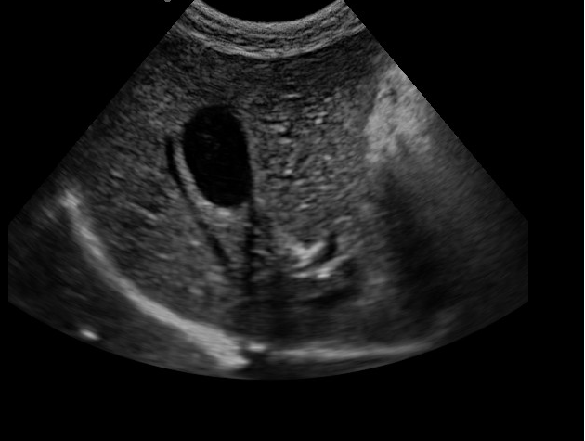

·顯示模式:B、B+B、4B、B+M、M、PW

·具有專業的動物產科軟件包,分別是狗、貓、馬、牛、羊

·適用于各種動物的臨床腹部、胸腔,心臟、肌腱、小器官、眼球、生殖系統等的檢查